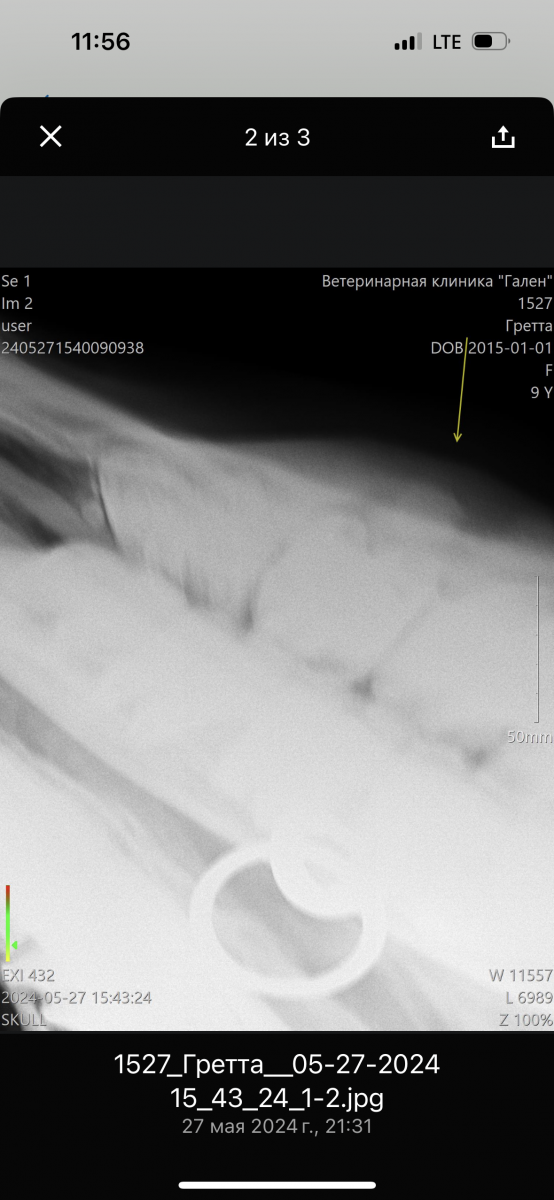

Далее сделали рентген (прилагаю его), врач заподозрил может киста, во рту ничего не нашли (думали на зуб), корни зубов хорошие, десна все тоже.